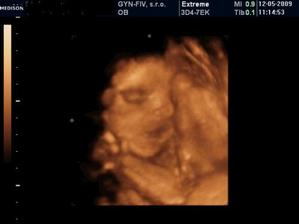

2.2. - drobcek ma 4,2 cm a vsetko je ok. tesime sa a mame aj prvu fotecku :o)...netrpezlivo cakame dalsiu poradnu 2.3.

8.3. - 3D UTZ - vraj to bude dievcatkooooooo :o))